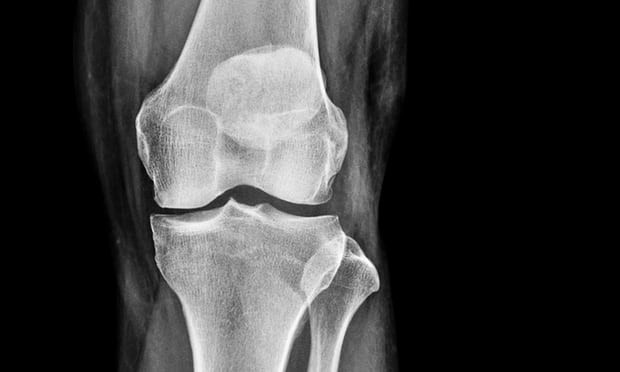

Hình minh họa